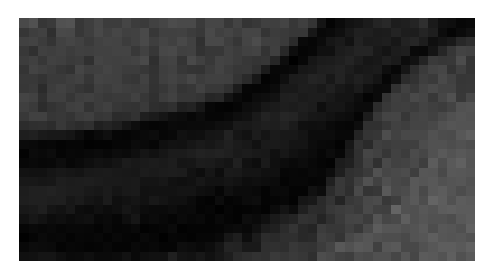

Figure 3: Reconstructions results. Rows 1 and 3: Examples of comparing the ground truth (GT) fully sampled image to the reconstructed images obtained by the three models (1-3), NPB-REC, baseline, E2E-VarNet trained with Dropout, and the NPB-REC std. map at accelerations R=4𝑅4R=4italic_R = 4, R=8𝑅8R=8italic_R = 8, respectively. Rows 2 and 4: The corresponding annotated ROIS of Nonspecific white matter lesions.

Fig. 3 presents examples of reconstruction results obtained by (1) our NPB-REC approach, (2) the baseline, and (3) Monte Carlo Dropout, for equispaced masks with two different acceleration rates R=4𝑅4R=4italic_R = 4 and R=8𝑅8R=8italic_R = 8. The reconstructed images predicted by the three models are smoother than the reference image. This is due to the fact that all the models were trained with SSIM loss, which tends to produce overly smooth reconstructions while preserving the diagnostic content and the anatomical features Sriram et al. (2020a). These images can be enhanced by dithering the image by adding a small amount of random Gaussian noise to produce a more textured reconstruction, as proposed in Sriram et al. (2020b).

Table 1 presents the mean PSNR and SSIM metrics, calculated over the whole inference set, for the three models. Our NPB-REC approach achieved significant improvements over the other methods in terms of PSNR and SSIM (Wilcoxon signed-rank test, pmuch-less-than\ll1e-4, except for SSIM values in line W, R=4𝑅4R=4italic_R = 4 where they are roughly the same for NPB-REC and Baseline). The improvement in the reconstruction performance can be noted both quantitatively from the metrics, especially for masks with acceleration rate R=8𝑅8R=8italic_R = 8, and qualitatively via the images of annotations, where our results show less smoothness than those obtained by Dropout.